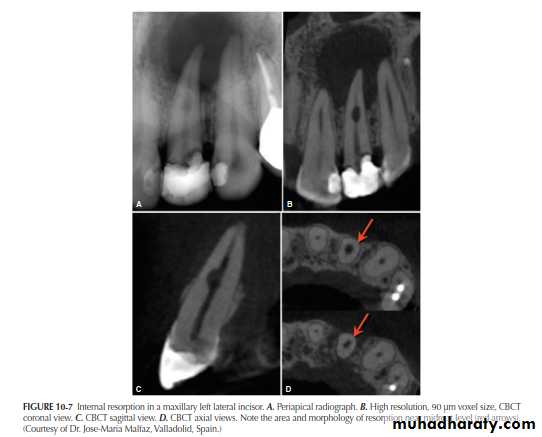

THE ADVENT OF CBCT AND THE THIRD PLANE OF VISUALIZATON

CBCT has been optimized for dental applications. Smaller fields of view and higher resolution scans appear to be ideal for endodontic use and may impact the nature of endodotic practice and radiographic decision-making in the near Future. One of the disadvantages of CBCT use is cost and access to the technology. However, with time, costs should continue to decrease and access to increase

A major advantage of CBCT is the visualization of anatomic

structures in three planes, generally referred to as coronal, axial (transverse), and sagittal reconstructions. CBCT technology also allows for panoramic and oblique reconstructions in addition to anatomic-specific reformatting such as temporomandibular joint (TMJ) improved the sensitivity and specificity of accurately detecting lesions or conditions affecting the jaws